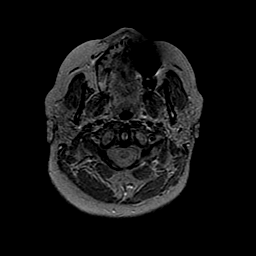

MR Study #2 -- Slice #3